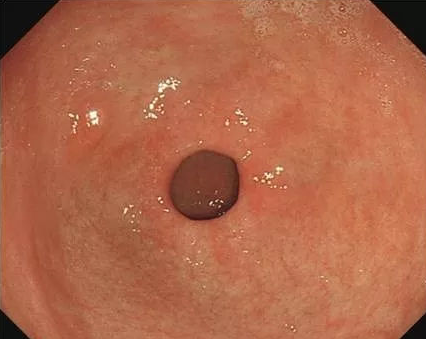

【萎缩性胃炎|萎缩性胃炎能完全治愈?先要辨别清楚是生理性还是病理性的!】慢性胃炎分为两种 , 一种是浅表性胃炎(也就是非萎缩性胃炎) , 另一种则是萎缩性胃炎 。 前者是指粘膜的充血、水肿及糜烂;后者则指胃黏膜胃固有腺体减少 , 常伴有肠上皮化生 。

本文图片